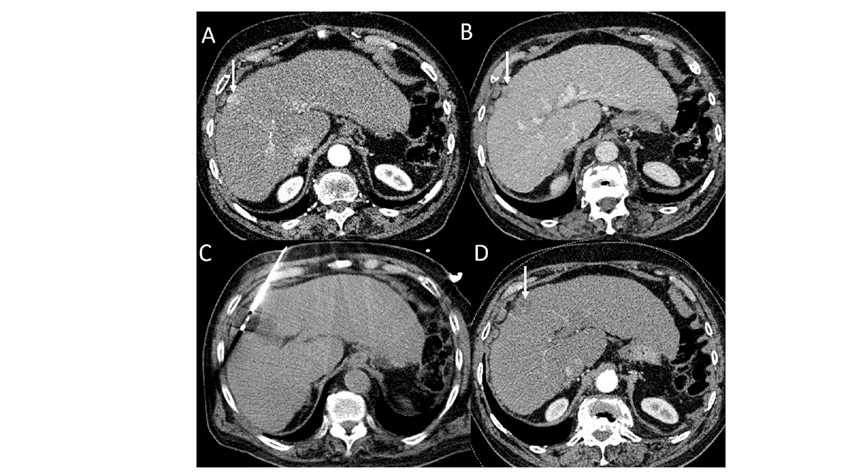

胆囊附近转移灶(来自子宫颈癌)的冷冻消融术

(A)门静脉期 CT 图像显示胆囊附近有病变(箭头)。

(B) PET-CT 图像显示病变处(箭头)。

(C) 手术过程中CT 显示冷冻探针位于病灶内。

(D)消融手术后 1 个月CT 显示完全消融。

CT引导的冷冻消融

undefined

51岁男性患者,肝移植后复发病例

(a) 射频消融后在病变边缘显示残余增强。

(b) 冷冻消融术中影像显示冰球完全覆盖病变。

(c) 19个月后随访,没有发生局部肿瘤进展。